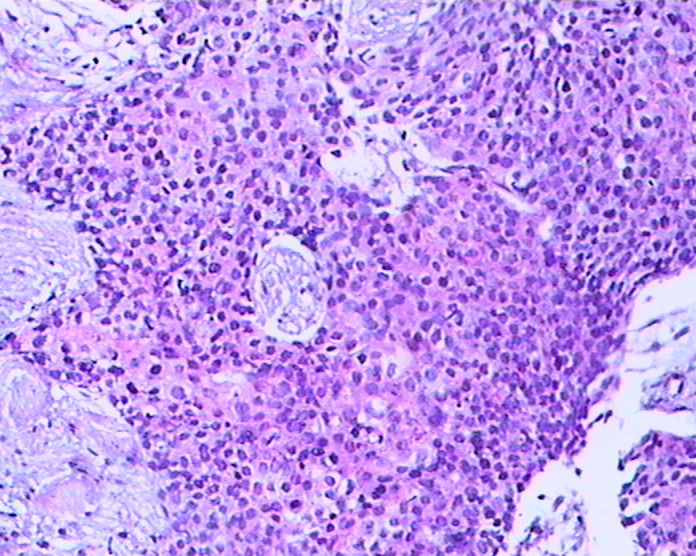

患者男性,51岁,发现右纵膈肿物,行穿刺活检。

参考诊断

鳞癌?

1。胸腺癌?

2.低分化鳞癌?

胸腺癌?